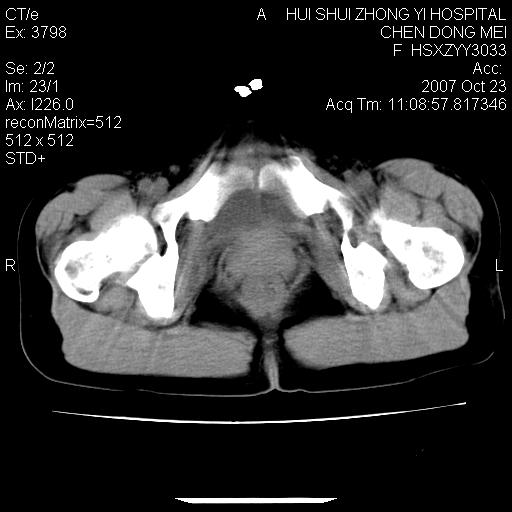

标题: CT10156:女.43岁,发现中下腹部包都块2年 [打印本页]

标题: CT10156:女.43岁,发现中下腹部包都块2年

发现中下腹部包都块2年。2年来月经不规律。

病灶内可见脂肪密度影,考虑畸胎瘤可能性大

病变巨大,呈囊实性改变,包膜较厚且完整,内见分膈,周围脏器明显受压移位,病变与左侧附件关系密切,考虑来源左侧附件的囊腺瘤,不除外癌变可能;畸胎瘤可能性较小。

病变巨大,呈囊实性改变,包膜较厚且完整,内见分膈,周围脏器明显受压移位,病变与左侧附件关系密切,考虑来源左侧附件的囊腺瘤,盆腔内见肿大淋巴结,不除外癌变可能。

腹膜后可见肿大的淋巴结,卵巢囊腺癌可能性大